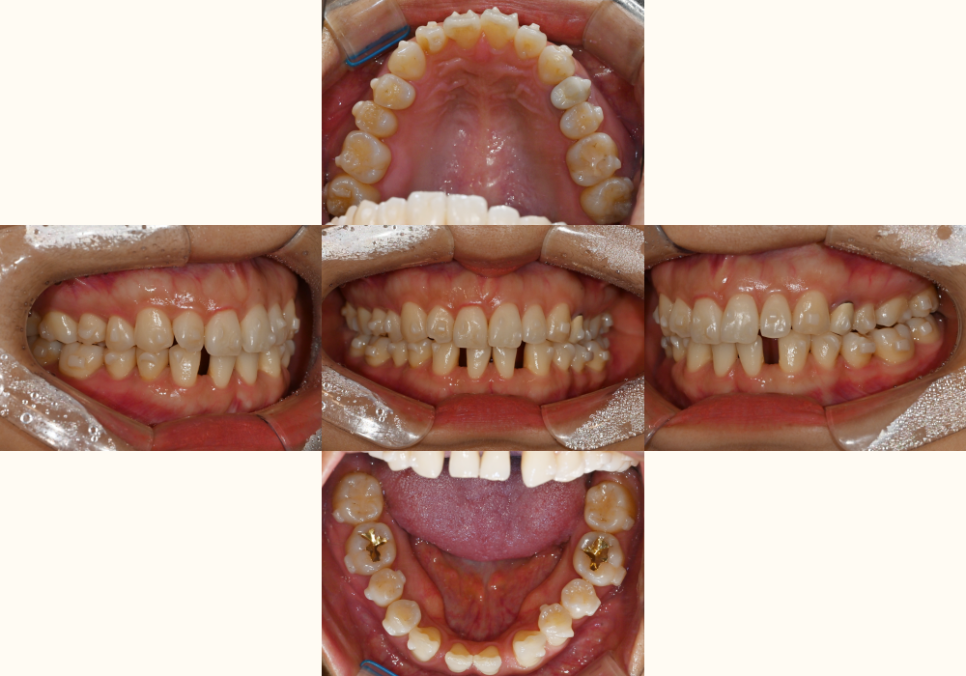

| 2. 정밀한 초진 검사가 성공의 첫걸음

23.10.20

먼저 구강 내 전체 상황을

파악하는 것부터 시작합니다.

위 사진을 보면

전체적으로 치열이 틀어져 있는 것을

확인할 수 잇었으며

결손된 부위로 인해

아랫니가 벌어져 있는 것을

확인할 수 있습니다.

양쪽 교합을 확인해 보면

왼쪽 어금니 부위가

반대교합이 확인됩니다.

윗니는 삐뚤빼뚤하며

위 앞니가 아랫니를 덮는 양이 부족합니다.

교합면을 보았을 땐

아래 앞니 2개가 결손되어 있으며

사이 공간이 있습니다.

위아래 앞니 사이 거리가 과도합니다.